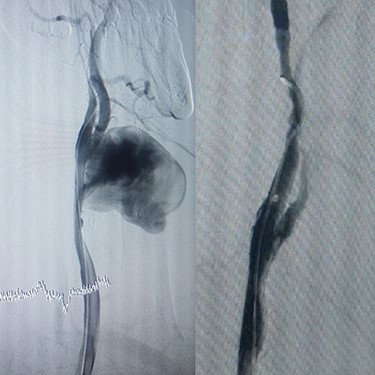

Case 4 – A 32-year-old man who was a known case of BD presented to the emergency department with a complaint of abdominal pain. In the abdominal CT scan, he had a thrombosed abdominal infrarenal aortic aneurysm (Fig. 5A). Heparin therapy was started. A huge right subclavian artery aneurysm was found in CTA (Fig. 5B). We talked to the patient about endovascular repair of the subclavian aneurysm but he refused the surgical treatment. Tablet of prednisolon (5 mg) twice a day was prescribed. In 1-year follow-up, the aneurysm size of the subclavian artery did not expand and his lower limbs were not symptomatic.

(A) Infra renal aortic thrombosis (down), (B) right subclavian aneurysm (up).